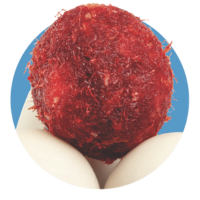

| New Bone Formation Potential Fibers were readily mineralized as early as 6 weeks when cultured in vivo indicating graft factors can promote bone-forming cells to mineralize the graft given the appropriate microenvironment4† | |||

| Hemostatic Facilitates coagulation to stop bleeding4† | |||